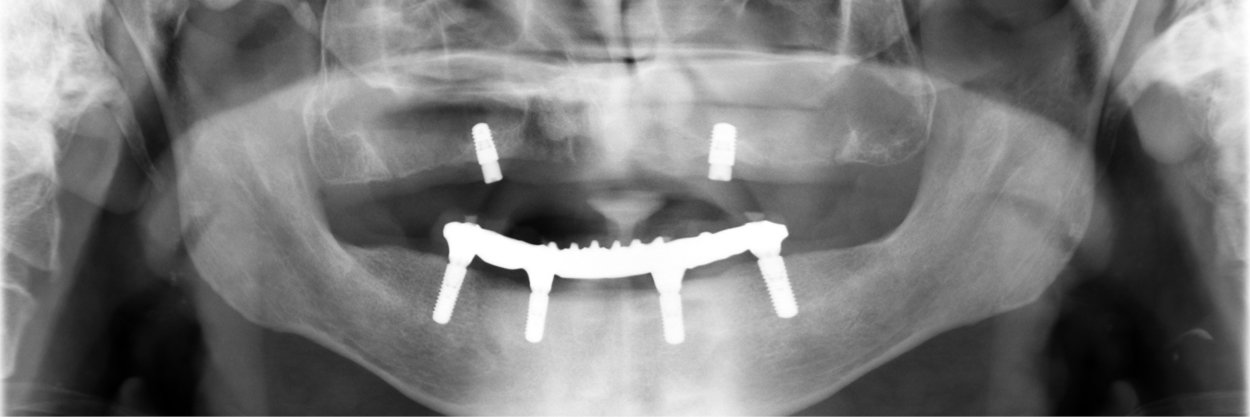

- Kostnadseffektivt arbetsflöde vid kombinationsprotetik på både tänder och implantat

- Overdentures – mekaniska aspekter och fallgropar